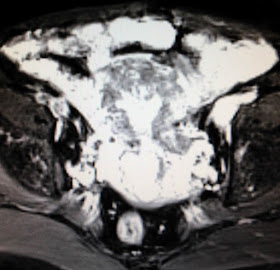

Women 52 yo  post menopause  2 years, vaginal bleeding.

MRI  with gado.

MRI1= uterine cavity is  large  and thickening  endometrium,  some filling defected at fundus of uterus.

MRI2=longitudinal scan showed  the  abnormal endometrium  penetrated to uterus muscle.

Based on  clinical status , ultrasound and MRI, ObGy doctor suggested that  endometrium carcinoma.